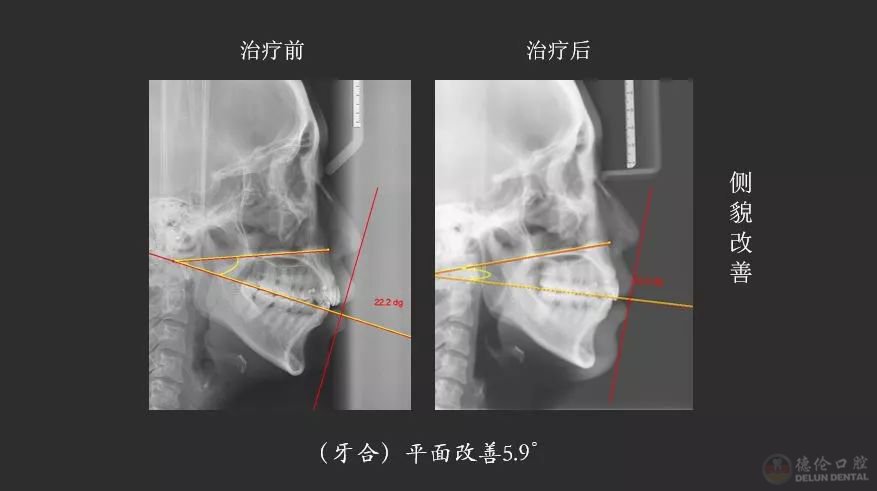

▲获奖病例侧貌X线前后对比

“按照常规方案,这种情况是不太适合推磨牙远移,因为推磨牙远移会造成整个颌平面的顺时针旋转,就会出现面型更不好看。但是因为给她设计了压低、另外打了支抗钉来控制它的矢状向和垂直向,就没有出现顺时针旋转,反而出现了整个颌平面的逆时针旋转,下巴还变好看了。”

熊小琴主任在接受访问时解释道,此案例的难点在于垂直向控制,在没有给患者进行手术的情况下解决了患者主诉、满足了个性化要求,矫牙结束后患者自己感觉很满意。